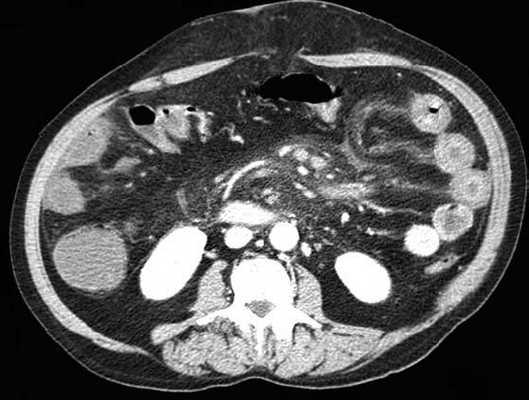

(Слева) На аксиальной КТ с контрастным усилением, выполненной мужчине 27 лет, у которого появилась боль и рвота, определяется, что тонкая кишка целиком, включая двенадцатиперстную кишку, располагается справа от средней линии. Слепая кишка расположена центрально, а ободочная кишка — справа от средней линии.

(Справа) На рентгенограмме, полученной при рентгеноскопии верхних отделов ЖКТ у этого же пациента, определяется частичная обструкция на уровне дистальных отделов двенадцатиперстной кишки, которая не пересекает среднюю линию, но имеет своеобразный вид, напоминающий букву Z или «штопор». На операции подтвердилась мальротация и обструкция двенадцатиперстной кишки, обусловленная тяжами (Ледда).

3. КТ при мальротации кишечника:

• Позволяет оценить расположение всех отделов кишечника

• Верхняя брыжеечная вена (ВБВ) занимает более вентральное положение либо находится слева от верхней брыжеечной артерии (ВБА):

о Заворот центральной части пищеварительной трубки характеризуется симптомом «водоворота» или «вихря», который формируется при скручивании брыжеечных сосудов и кишки

(Слева) На аксиальной КТ, выполненной женщине 4 7 лет с жалобами на боль, определяется, что верхняя брыжеечная артерия и вена находятся в положении, обратном типичному, а тонкая кишка целиком расположена в брюшной полости с правой стороны. Определяется утолщение стенки тощей кишки и ограниченный асцит, а также расширение просвета кишки.

(Справа) На аксиальной КТ с контрастным усилением у этой же пациентки визуализируются другие сегменты тощей кишки с утолщенной стенкой. Мальротация подтвердилась на операции наряду с ишемическими изменениями тощей кишки, которая была пережата из-за спаек.